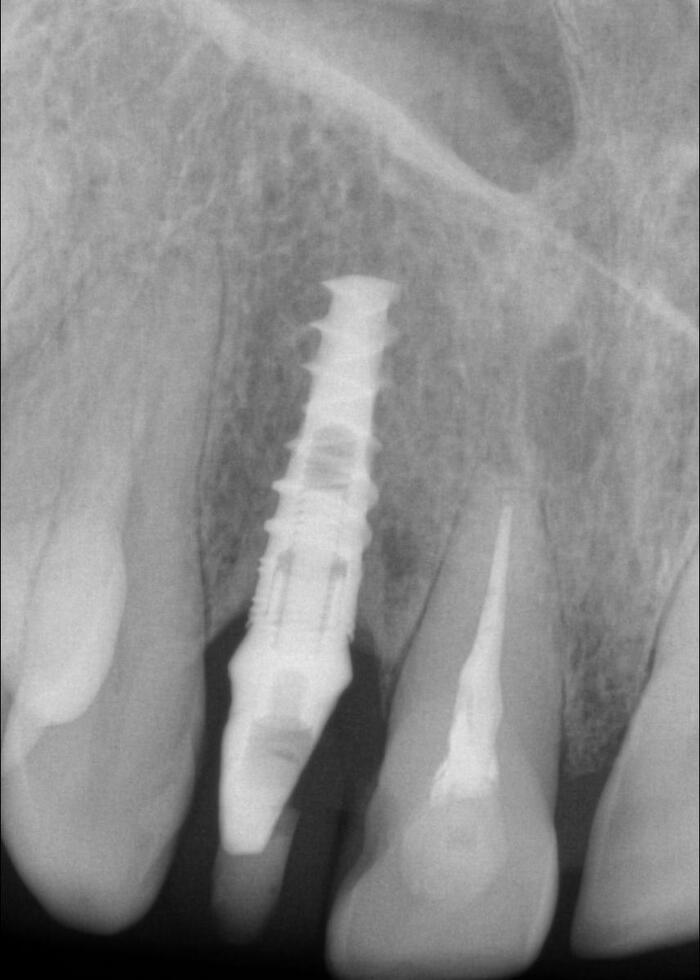

Согласитесь, не особо эстетично. Ортопантомограмма:

Фрагмент компьютерной томографии (вид сбоку):

Контрольная ортопантомограмма:

Прицельный снимок: